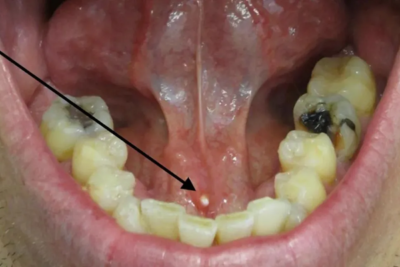

Salivary gland stones are hardened mineral deposits that form within the glands and block saliva flow. This leads to pain, swelling, and sometimes infection. Choosing the right sialolithiasis treatment is essential for restoring normal gland function.

With advancements in advanced salivary care and salivary gland blockage treatment, patients can now avoid complications and achieve better outcomes through modern techniques.